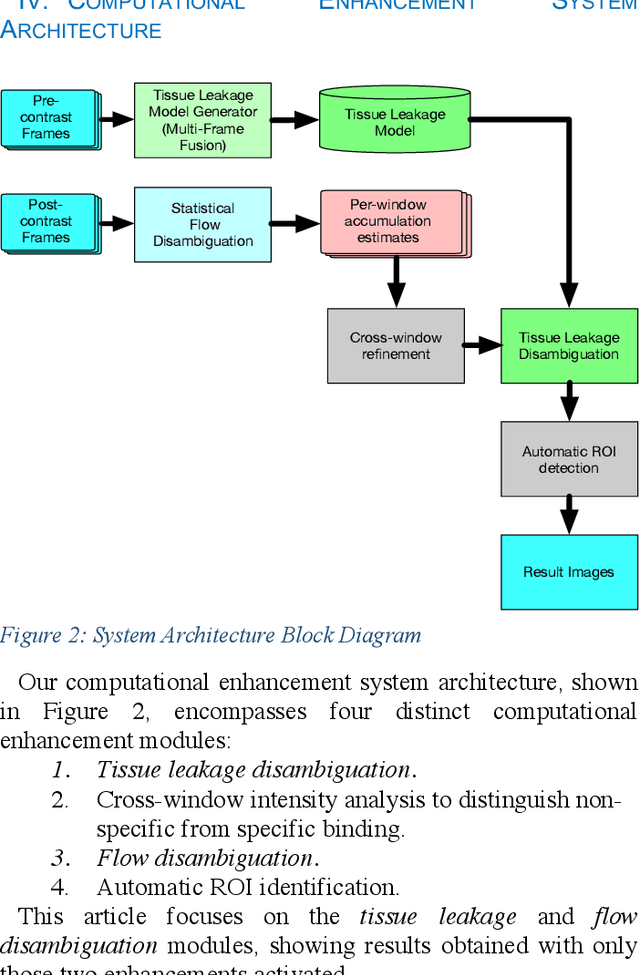

Molecularly targeted contrast enhanced ultrasound (mCEUS) is a clinically promising approach for early cancer detection through targeted imaging of VEGFR2 (KDR) receptors. We have developed computational enhancement techniques for mCEUS tailored to address the unique challenges of imaging contrast accumulation in humans. These techniques utilize dynamic analysis to distinguish molecularly bound contrast agent from other contrast-mode signal sources, enabling analysis of contrast agent accumulation to be performed during contrast bolus arrival when the signal due to molecular binding is strongest. Applied to the 18 human patient examinations of the first-in-human molecular ultrasound breast lesion study, computational enhancement improved the ability to differentiate between pathology-proven lesion and pathology-proven normal tissue in real-world human examination conditions that involved both patient and probe motion, with improvements in contrast ratio between lesion and normal tissue that in most cases exceed an order of magnitude (10x). Notably, computational enhancement eliminated a false positive result in which tissue leakage signal was misinterpreted by radiologists to be contrast agent accumulation.